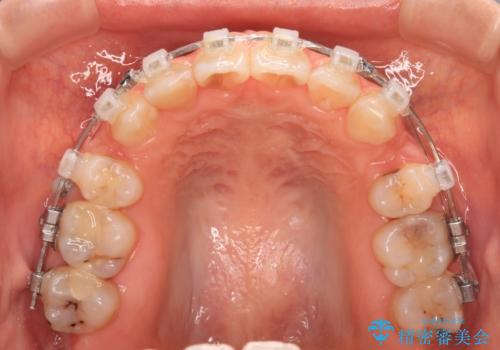

- 矯正装置

- クリアブラケット

- 前歯のデコボコと口元の突出感を気にして来院された患者様です。

口元の突出感が認められ、更には左右で異なる咬合状態であったため、下顎右側は第二小臼歯を、左側は第一小臼歯を抜去することでバランスを取るような治療計画としました。

また上顎前歯は大臼歯に補綴治療が必要であったため、矯正治療後にオールセラミッククラウンによる補綴治療を行うこととしました。

下顎の抜歯位置を左右で変えることで、最終的に上下正中をほぼ一致させることができました。